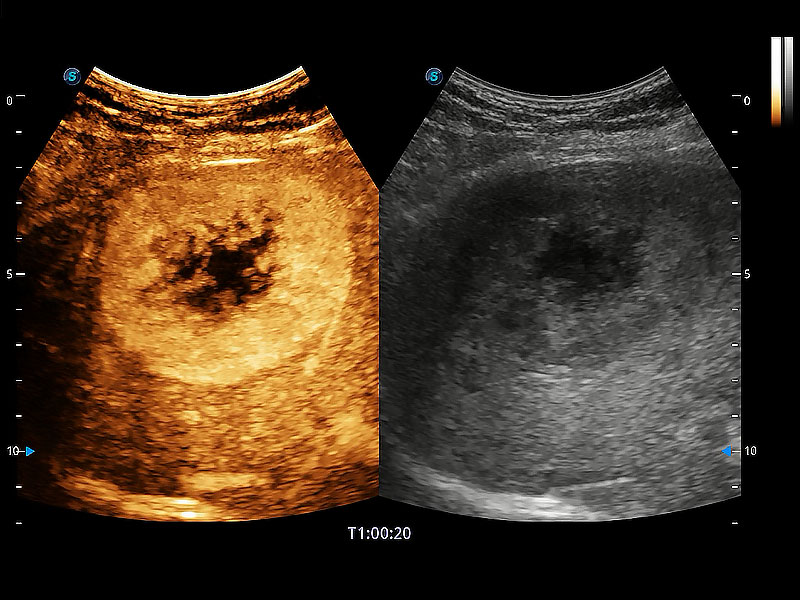

非线性融合造影成像充分利用谐波和基波信号,为难以观察的血流进行增强显像。可用于线阵、凸阵、微凸阵、相控阵探头。